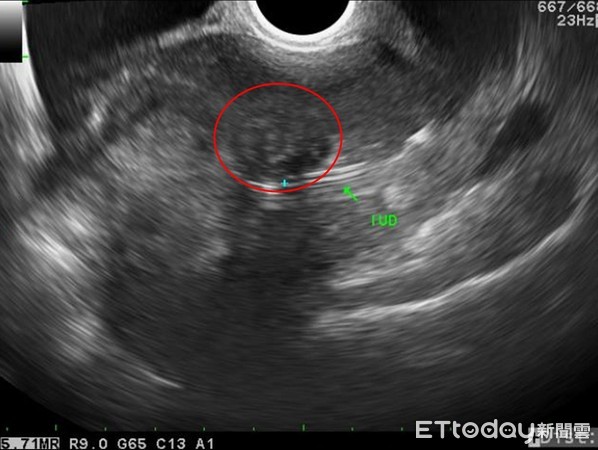

▲手術前檢查出的子宮肌瘤。(圖/花蓮慈院提供)

36歲的高小姐因月經血量異常到醫院求診,經門診子宮肌鏡檢查,發現有一顆約3公分的肌瘤,由於生長部位較深層,只能透子宮腔鏡內視鏡手術刮除,所幸經切片檢查,證實為良性肌瘤,也讓她大大鬆一口氣。

收治患者的花蓮慈濟醫院婦產部主治醫師陳萱表示,子宮肌瘤是婦女常見的疾病之一,最常見的症狀為經期大量出血,或者點點滴滴流不停。雖然超音波就可揪出子宮肌瘤,但如果在比較深的肌肉層或漿膜層,光靠超音波難以發現,但若透過子宮腔鏡檢查,就能及早找出病灶。